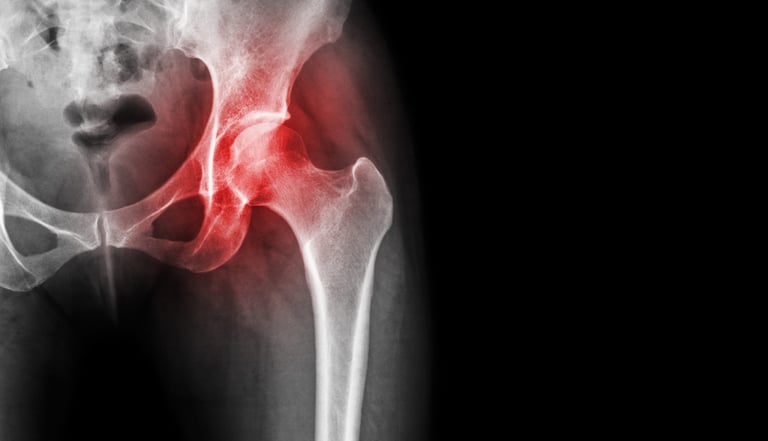

Avascular Necrosis (AVN)

Avascular necrosis is a disease that results from the temporary or permanent loss of blood supply to the bone. When blood supply is cut off, the bone tissue dies and the bone collapses. If avascular necrosis happens near a joint, the joint surface may collapse. This condition may happen in any bone.